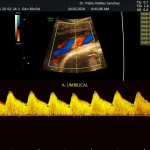

- La vitalidad y el bienestar fetal (Doppler).